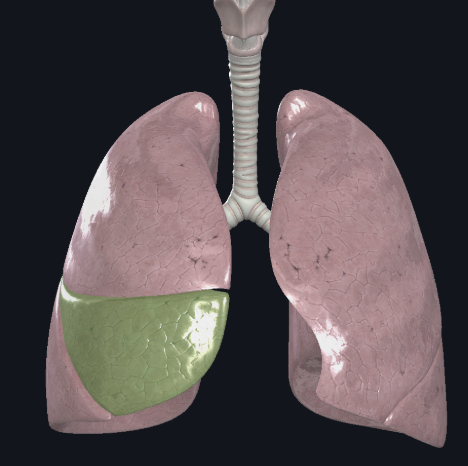

Middle lobe of the right lung

What structure is this?

Horizontal fissure of right lung

What structure is this?